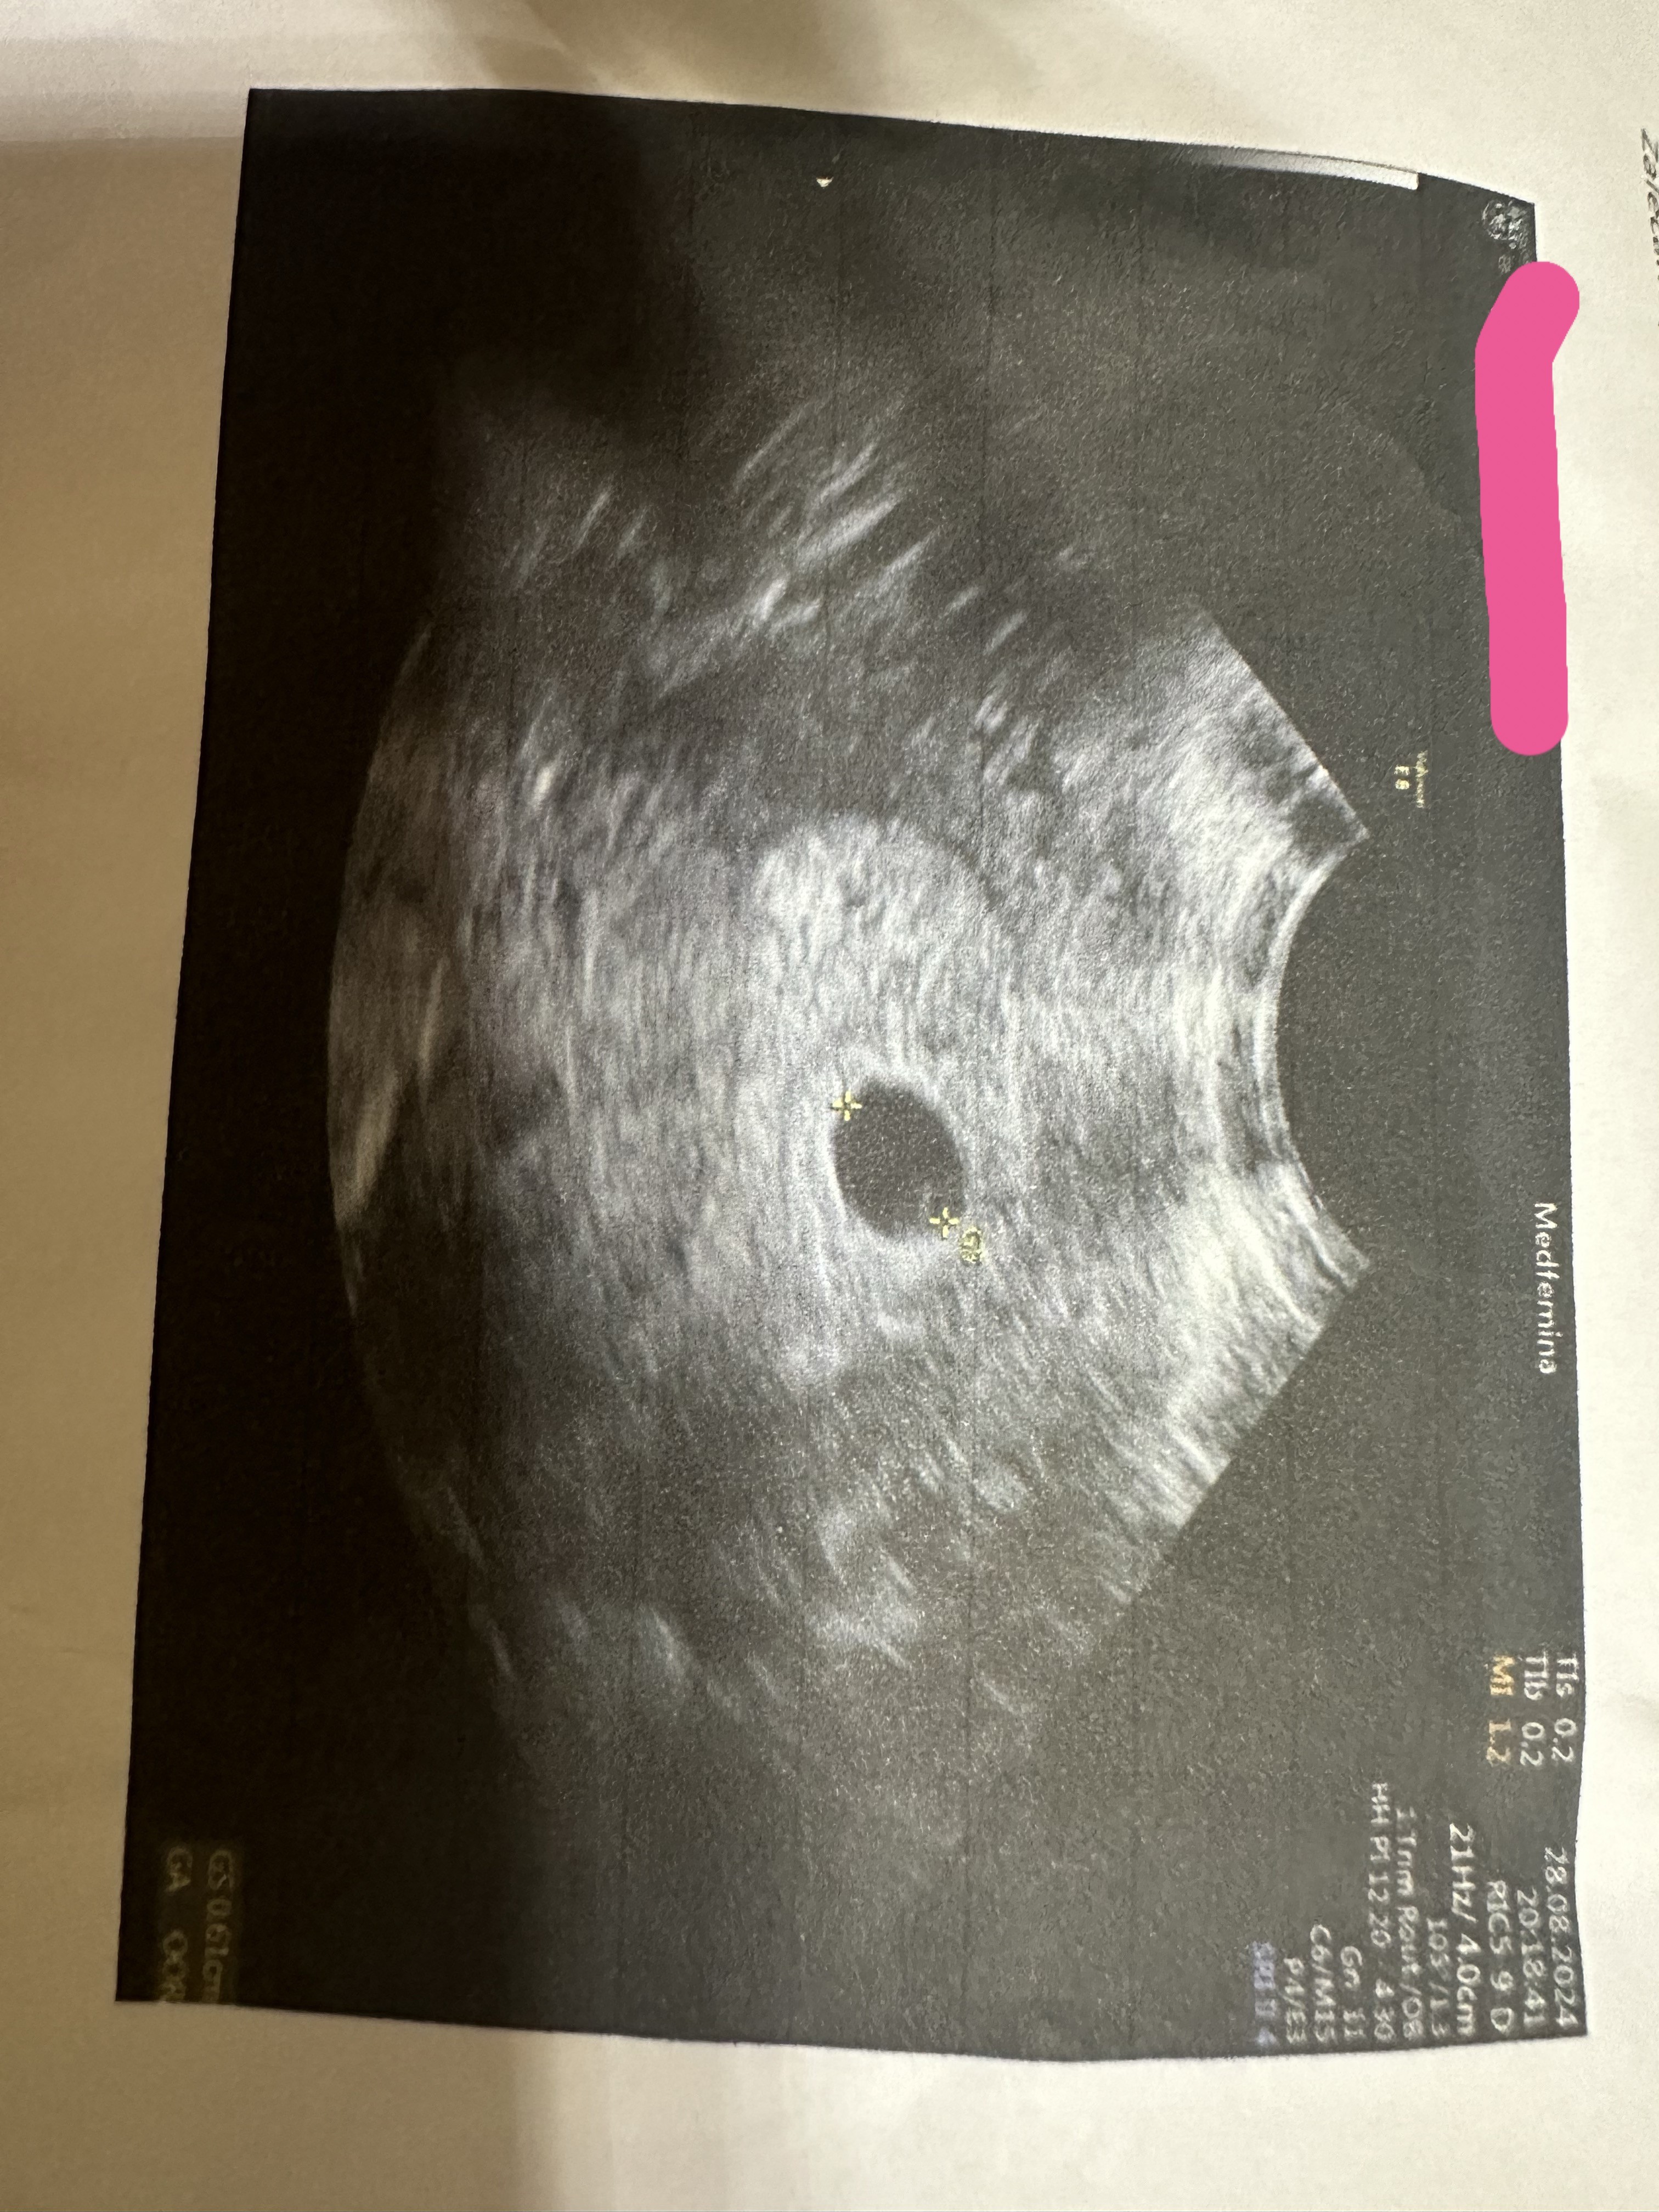

Cześć dziewczyny ☺️ Jestem po 3 poronieniach… obecnie jestem w ciąży (wg ostatniej miesiączki 5t 4d). Przyjmuję zastrzyki neoparin i duphaston. Oczywiście już schodki… lekarz mi powiedział, że USG wygląda na 5t2d.. ale dla mnie, po moich doświadczeniach, ten pęcherzyk (0,61cm) jest za mały nawet jak na 5t2d… myślicie że coś z tego może być? Kazał mi przyjść za tydzień, żeby zobaczyć czy prawidłowo rośnie… dzisiaj byłam na becie, w sobotę powtórka z rozrywki 🥹

• IMG_7221.jpeg

IMG_7221.jpeg

1,9 MB · Wyświetleń: 72